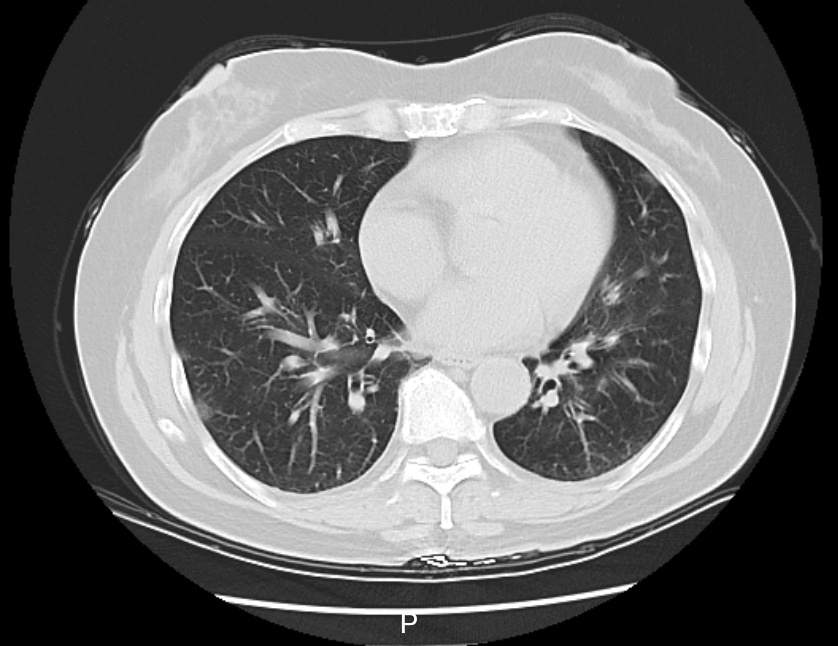

接诊的庞医生了解到,李阿姨在当地接受了一些治疗,但体温仍居高不下。家中同行的6个人,有5个人都先后发烧了。庞医生判断,李阿姨大概率是得了传染性较强的呼吸道疾病,立即给她安排了血常规、相关病毒抗原检测,以及更清晰的肺部CT检查,以便进一步了解病情。

检测结果显示,李阿姨已经得了病毒性肺炎,甲型流感病毒核酸呈阳性。这一下,罪魁祸首找到了,是甲流搞砸了这一家人一次本该圆满的旅行。

图|李阿姨肺部CT影像